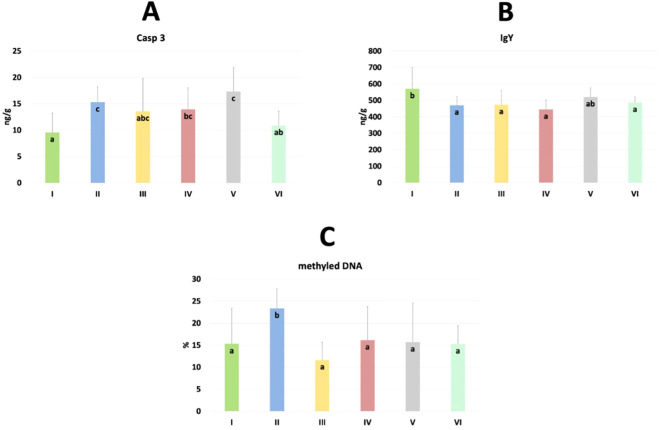

The results of selected indicators of epigenetic and oxidative changes in chicken jejunum are shown in T3. Significant differences in caspase 3 (Casp 3), immunoglobulin Y (IgY), and % of methylated DNA levels are shown in f9. Casp 3 levels were significantly higher in the C. perfringens and CBD + nano-Se groups compared to the C and CBD + nano-Se + C. perfringens groups and significantly lower in the control group compared to the C. perfringens, nano-Se + C. perfringens and CBD + nano-Se groups (P=0.008). IgY levels were significantly lower in the C. perfringens, CBD + C. perfringens, nano-Se + C. perfringens, and infected groups fed both additives compared to the C group (P=0.031). The % of methylated DNA was significantly higher in the control infected group compared to all other groups tested (P=0.029). No significant difference was found between group C and the group challenged with CBD and nano-Se in % of methylated DNA. No significant differences were found between the other markers.

| Casp 3 [ng/g] | 9.576a | 15.305c | 13.569abc | 13.920bc | 17.322c | 10.881ab | 2.838 | 0.687 | 0.008* |

| IgY [ng/g] | 570.900b | 470.400a | 473.600a | 445.600a | 520.900ab | 487.300a | 44.708 | 11.999 | 0.031* |

| % of methylated DNA | 15.296a | 23.349b | 11.623a | 16.149a | 15.704a | 15.283a | 3.846 | 1.026 | 0.029* |

In the current experiment, epigenetic, immunological and oxidative changes as a response to treatment in the blood and jejunum of chickens were investigated. TNF-α is an important pro-inflammatory cytokine that plays a key role in immune responses during infection. It helps initiate and regulate the immune system response by promoting inflammation, cell survival, and elimination of pathogens. However, dysregulation or overproduction of TNF-α may contribute to chronic inflammation (ref. 57, ref. 58). In blood, significantly higher TNF-α in the CBD + C. perfringens group was found compared to the nano-Se + C. perfringens and CBD + nano-Se + C. perfringens groups. This may show a specific effect of this compound on the immune system. The increase in TNF-α levels may be related to an increase in the inflammatory response induced by the infection and suggests that the CBD supplement, rather than having an immunosuppressive effect, may have increased the inflammatory response in the context of this infection. Still, it should be noted that no significant difference was found between the control group and the infected group with one or two supplements. CBD is well known for its immunomodulatory effects (ref. 59, ref. 60), but there are studies indicating that in the bacterial response, it may also induce an increase in the production of pro-inflammatory cytokines (ref. 61, ref. 62). The increased TNF-α levels in the CBD-infected chicken group may be the organism’s attempt to counteract the stress stimuli through an enhanced inflammatory response. In this study, TNF-α expression was not altered by the C. perfringens challenge (C vs. C. perfringens group), which agrees with previous studies (ref. 63–ref. 65). The difference in TNF-α levels between the group of chickens supplemented with CBD alone and the group supplemented with both nano-selenium and CBD may be due to the synergistic effects of the two compounds. Nano-selenium, through its antioxidant and immune response modulating effects, may have reduced the pro-inflammatory effects of CBD alone, explaining the lower TNF-α levels in the group with the combination of these supplements, which is consistent with the results of Sendani et al. (ref. 66). On the other hand, the lack of a significant difference between the control group and the infected group with the addition of both nano-selenium and CBD may suggest that the combination of these two compounds has a balanced effect on the immune system, mitigating the excessive inflammatory response caused by the infection, allowing for a more controlled immune response. On the other hand, in the gut, significant differences were shown in the expression of Casp 3, IgY, and % of methylated DNA. Caspase 3 is a key enzyme in the process of programmed cell death (apoptosis). Casp 3 activation is often triggered in response to various stressors, leading to controlled cell death that helps maintain homeostasis and eliminate damaged cells (ref. 67). In this study, Casp 3 levels were significantly lower in the control group compared to the C. perfringens, nano-Se + C. perfringens, and CBD + nano-Se groups. This result contrasts the study of Guo et al. (ref. 46), who found a lack of significance in Casp 3 levels in C. perfringens-infected chickens. In contrast, this result aligns with the study by Huang et al. (ref. 68), which showed that infections can significantly increase caspase 3. However, the increase in this factor in the CBD + nano-Se and nano-Se + C. perfringens groups is not easy to explain. The possible action was that nano-selenium at the dose used in the experiment exhibits a pro-apoptotic effect, perhaps to accelerate the elimination of damaged cells. It is important to note that no significant differences were shown between the control group and the CBD + C. perfringens and CBD + nano-Se + C. perfringens groups, which is consistent with a study by de Fillips et al. (ref. 69), which showed that CBD reduces inflammation in patients with LPS-induced colitis and lowers Casp 3 levels. It can also be concluded that the beneficial effect of nano-selenium, in this case, may depend on synergism with cannabidiol, or cannabidiol could have reduced the potential pro-apoptotic effect of nano-selenium. Evaluation of the immunoglobulin Y concentration showed that it was significantly lower in all test groups compared to the control and non-infected group with cannabidiol and nano-selenium. In poultry, IgY is a type of special immunoglobulin that is produced by stimulation of specific antigens in vivo and has a similar function to immunoglobulin G (IgG) in mammals (ref. 70). However, very limited information is available on this immunoglobulin and C. perfringens infection in poultry and its concentration dependence on nano-selenium and cannabidiol. Decreased IgY concentrations in chickens with bacterial infections may indicate an impaired immune response, favoring further infection and intestinal barrier damage. This is consistent with a study by Cui et al. (ref. 70), who showed reduced levels of IgY mRNA expression in the jejunum after LPS treatment of E. coli in chickens. Contemporary research confirms that IgY supplementation in the context of pathogen control may have a supportive effect. Still, it may sometimes be ineffective, which may explain the lower concentration of this immunoglobulin in the study groups (ref. 71, ref. 72). Interestingly, IgY concentration in the control group and the non-infected group with the addition of CBD + nano-Se was at the same level. This indicates that the addition of cannabidiol and nano-Se does not, by themselves, reduce the concentration of IgY in chickens. The % of methylated DNA was significantly higher in the infected group compared to all other study groups, which is consistent with the results of Ognik et al. (ref. 11), which showed that C. perfringens infection increased the percentage of methylated DNA in the wall of the ileum in turkeys. DNA methylation is a key process regulating gene expression, which affects many cellular functions, including immune response, cell growth, and stress response. Evidence from in vivo and in silico studies shows that cannabidiol can regulate the activity of enzymes responsible for DNA methylation due to its direct binding to the enzymes and/or regulating their activity through neurotransmitter-mediated signaling (ref. 19, ref. 73). In a rodent model of iron-induced neurodegeneration, CBD normalized mitochondrial DNA methylation levels in the hippocampus (ref. 73). Toubhans et al. (ref. 74) showed that selenium can modulate histone methylation, highlighting its important role in redox biology. Both assumptions are consistent with the current results, as the results in the infected groups with additives and the control group were at similar levels. Given the above, it may be concluded that the lack of significance in the assays of the other parameters indicative of epigenetic and oxidative changes may be related to two main facts: (i) the C. perfringens infection was not sufficient to induce the full changes in the parameters studied, and (ii) the exposure to challenge factor was too short to bring about the aforementioned changes fully.